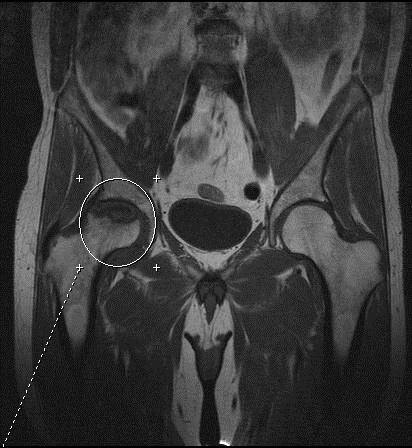

Стадии некроза сустава

Некроз сустава можно разделить на несколько стадий:

1. Исходная стадия: Начальные изменения в ткани, не выражающиеся симптомами.

2. Стадия омертвения: Явные признаки повреждения тканей, начинают проявляться болевые ощущения.

3. Стадия разрушения: Утрачиваются функции сустава, проявляются сильные боли, возможны деформации.

4. Окончательная стадия: Полное омертвение тканей, сустав перестает функционировать.